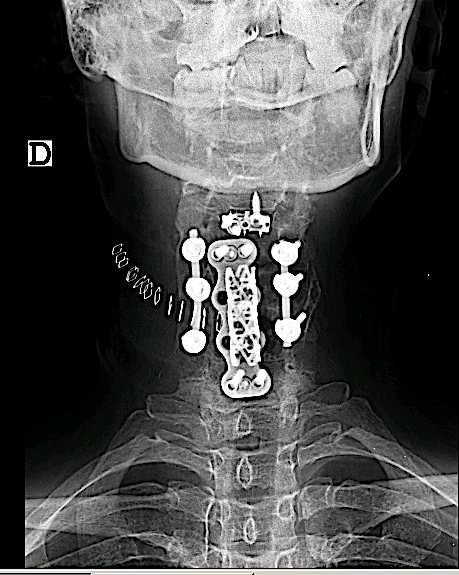

-El desarrollo de las cajas intersomáticas cervicales atornilladas plantea una solución sencilla y óptima bajo mi punto de vista:

- Respecto a la placa cervical: no es necesario retirarla (lo cual ahora bastante trabajo y riesgos si se trata de una corpectomía con injerto tipo malla como el caso que describo a continuación).

- Respecto a la caja intersomática (cage stand alone): su uso puede generar dudas en un nivel adyacente, con mayor exigencia mecánica.

Control postoperatorio